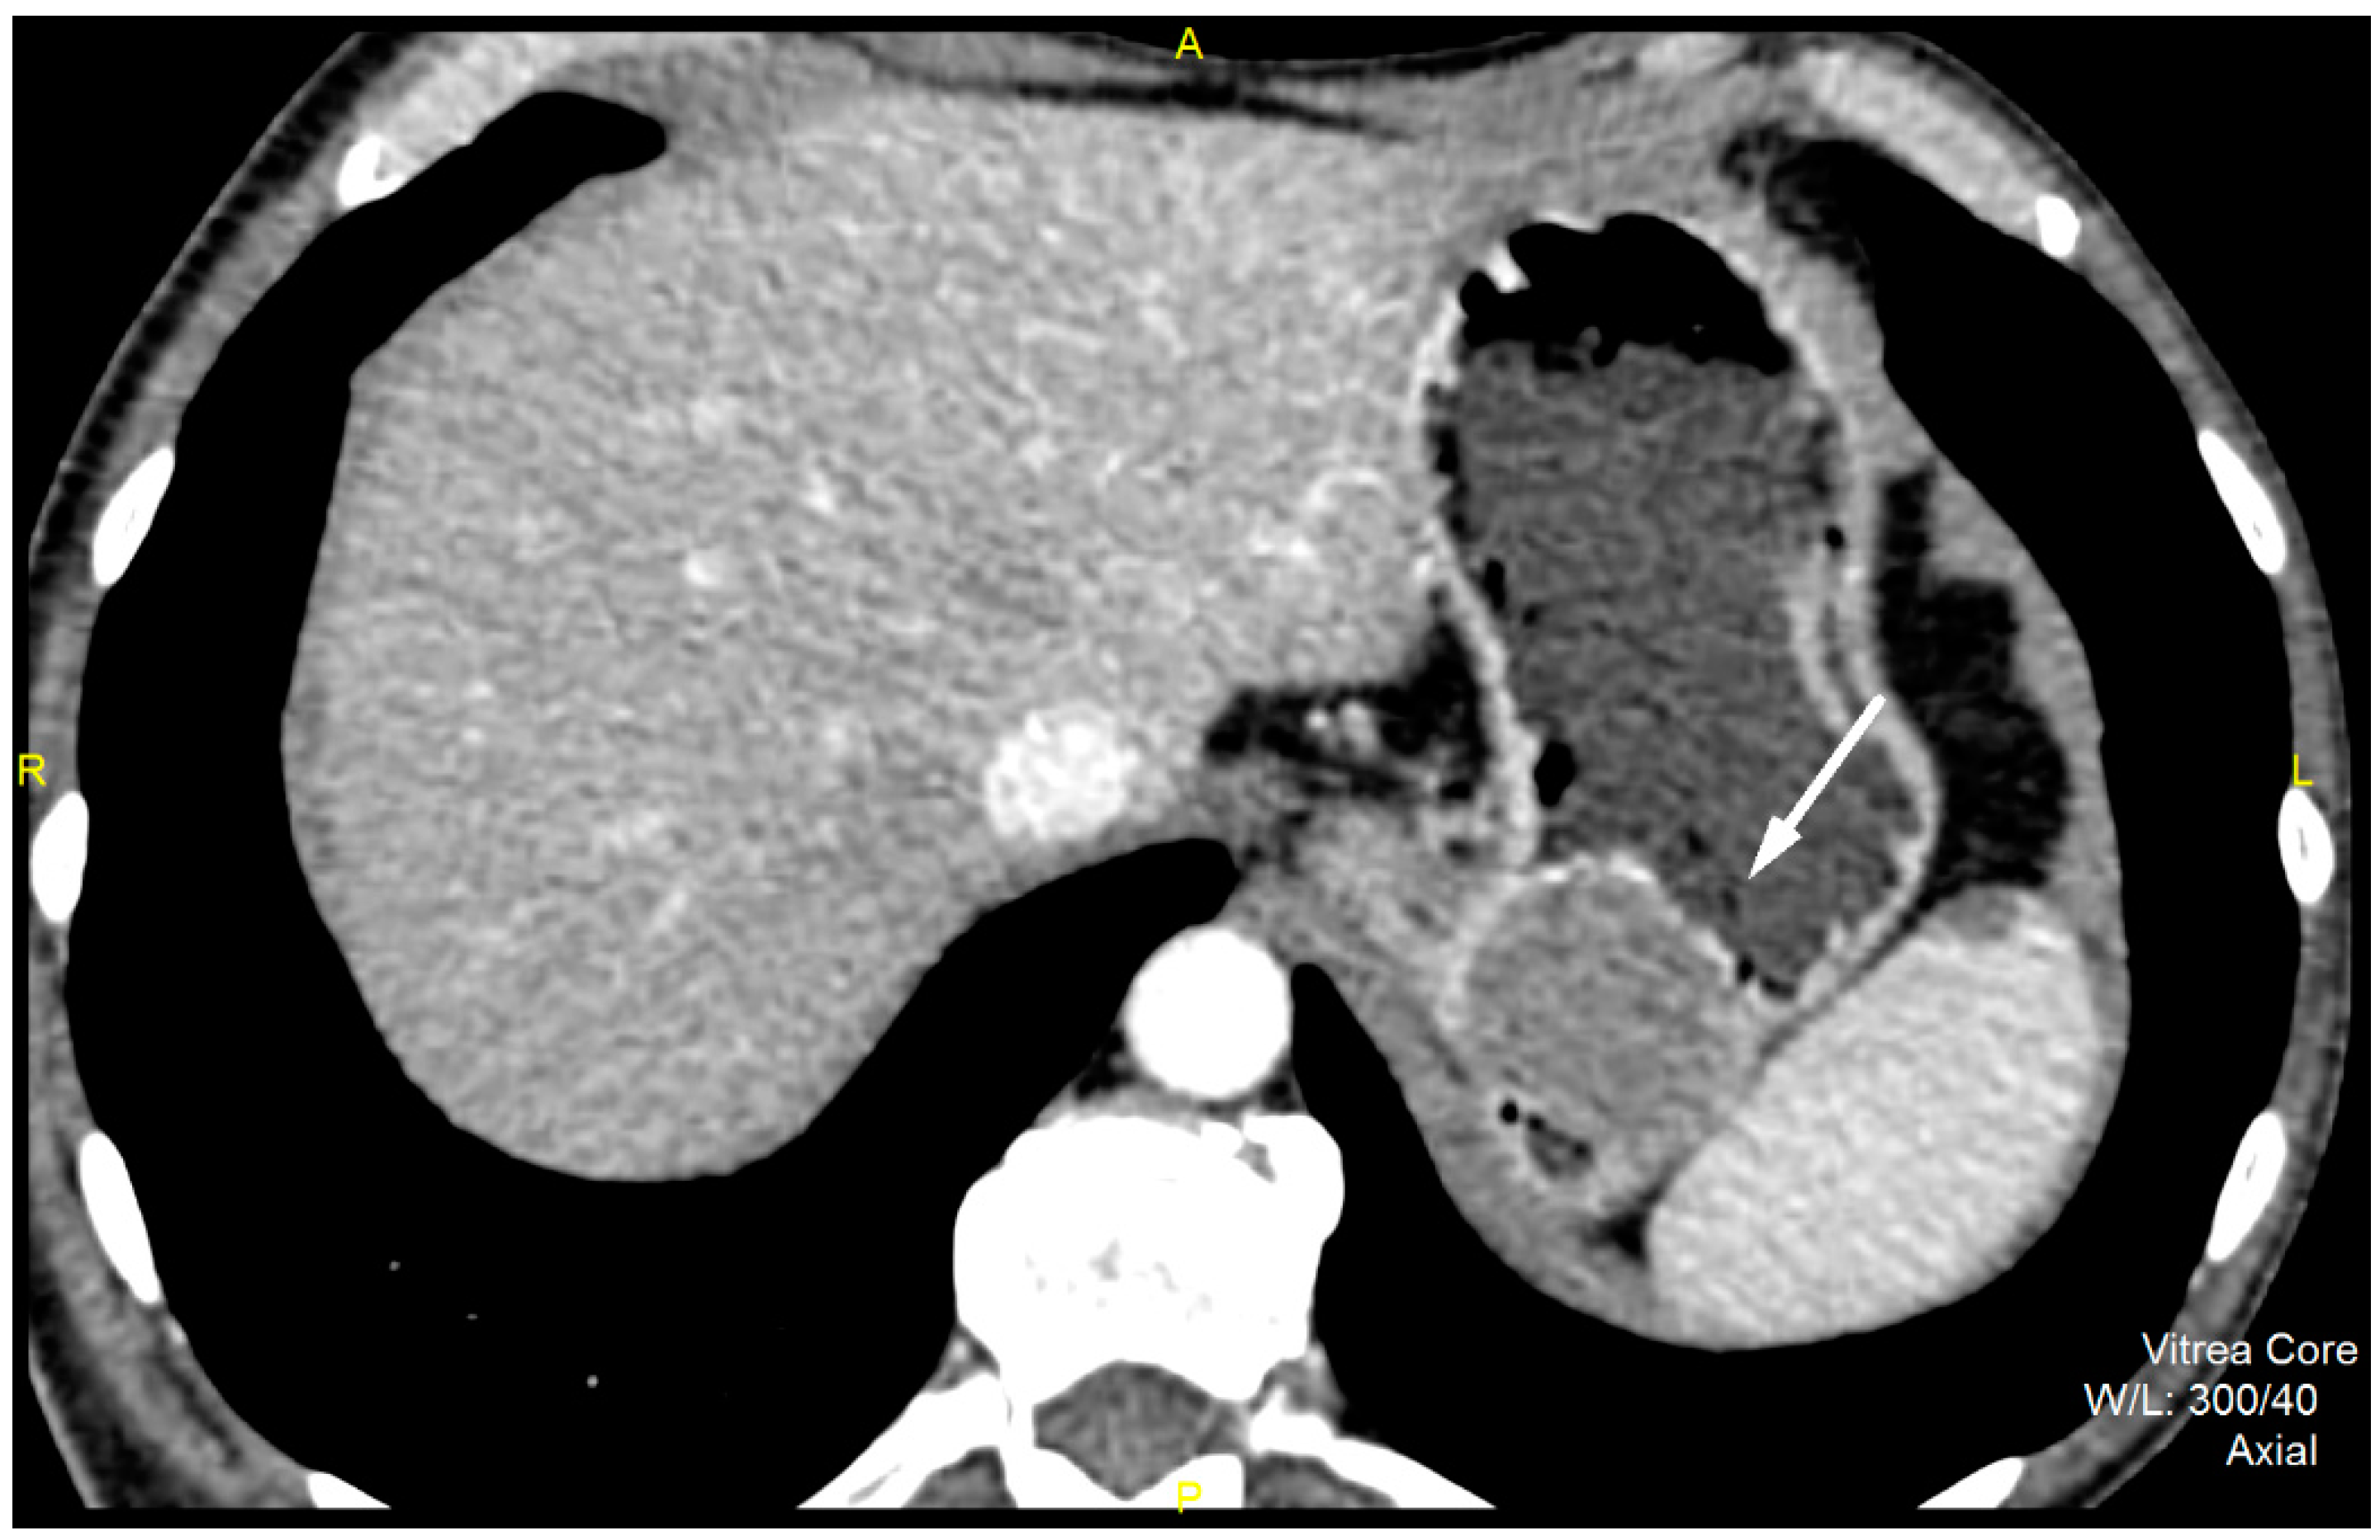

CT imaging features were analyzed as follows: maximal diameter in the axial slice and tumor structure, which was classified into cystic and solid/necrotic. The shape was depicted as regular or irregular. Tumor localization considered the body of the stomach, antrum or pyloric region. Mucosa was observed in two ways: intact/continuous or disrupted. Growth patterns were categorized as exophytic/mixed or endophytic. The degrees of enhancement of the solid part of tumor tissue were divided into weak, moderate or obvious enhancements. The presence of enlarged feeding or draining vessels (EFDV) was also recorded, as was the presence of metastasis in liver and other organs ( Figure 1, Figure 2 and Figure 3).

Figure 1. Contrast enhanced computed tomography of the abdomen, axial view, demonstrates low grade GIST (white arrow) in a 54-year old male patient as submucosal, with a round lesion with endophytic growth in the subcardial region of gastric body. The tumor has an approximate diameter of 45 mm, a solid structure with low post-contrast opacification, covered by an intact mucosa.